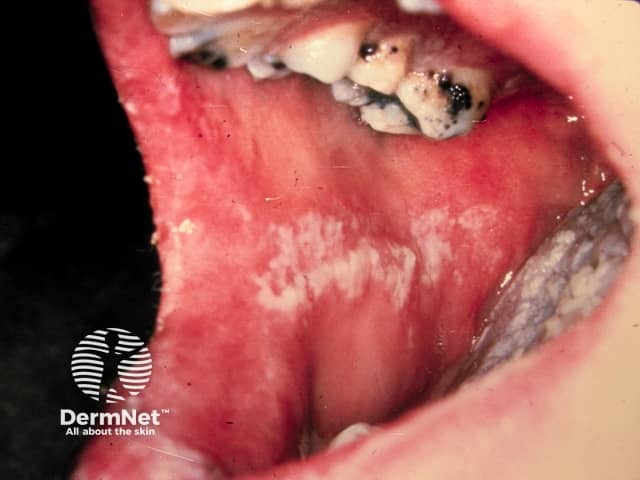

Stomatitis is inflammation of the mucous membrane of the mouth, including the inner aspect of the lips, cheeks, gums, tongue, and throat. It is a type of mucositis. It can be acute or chronic, mild or serious.

Erosive lichen planus